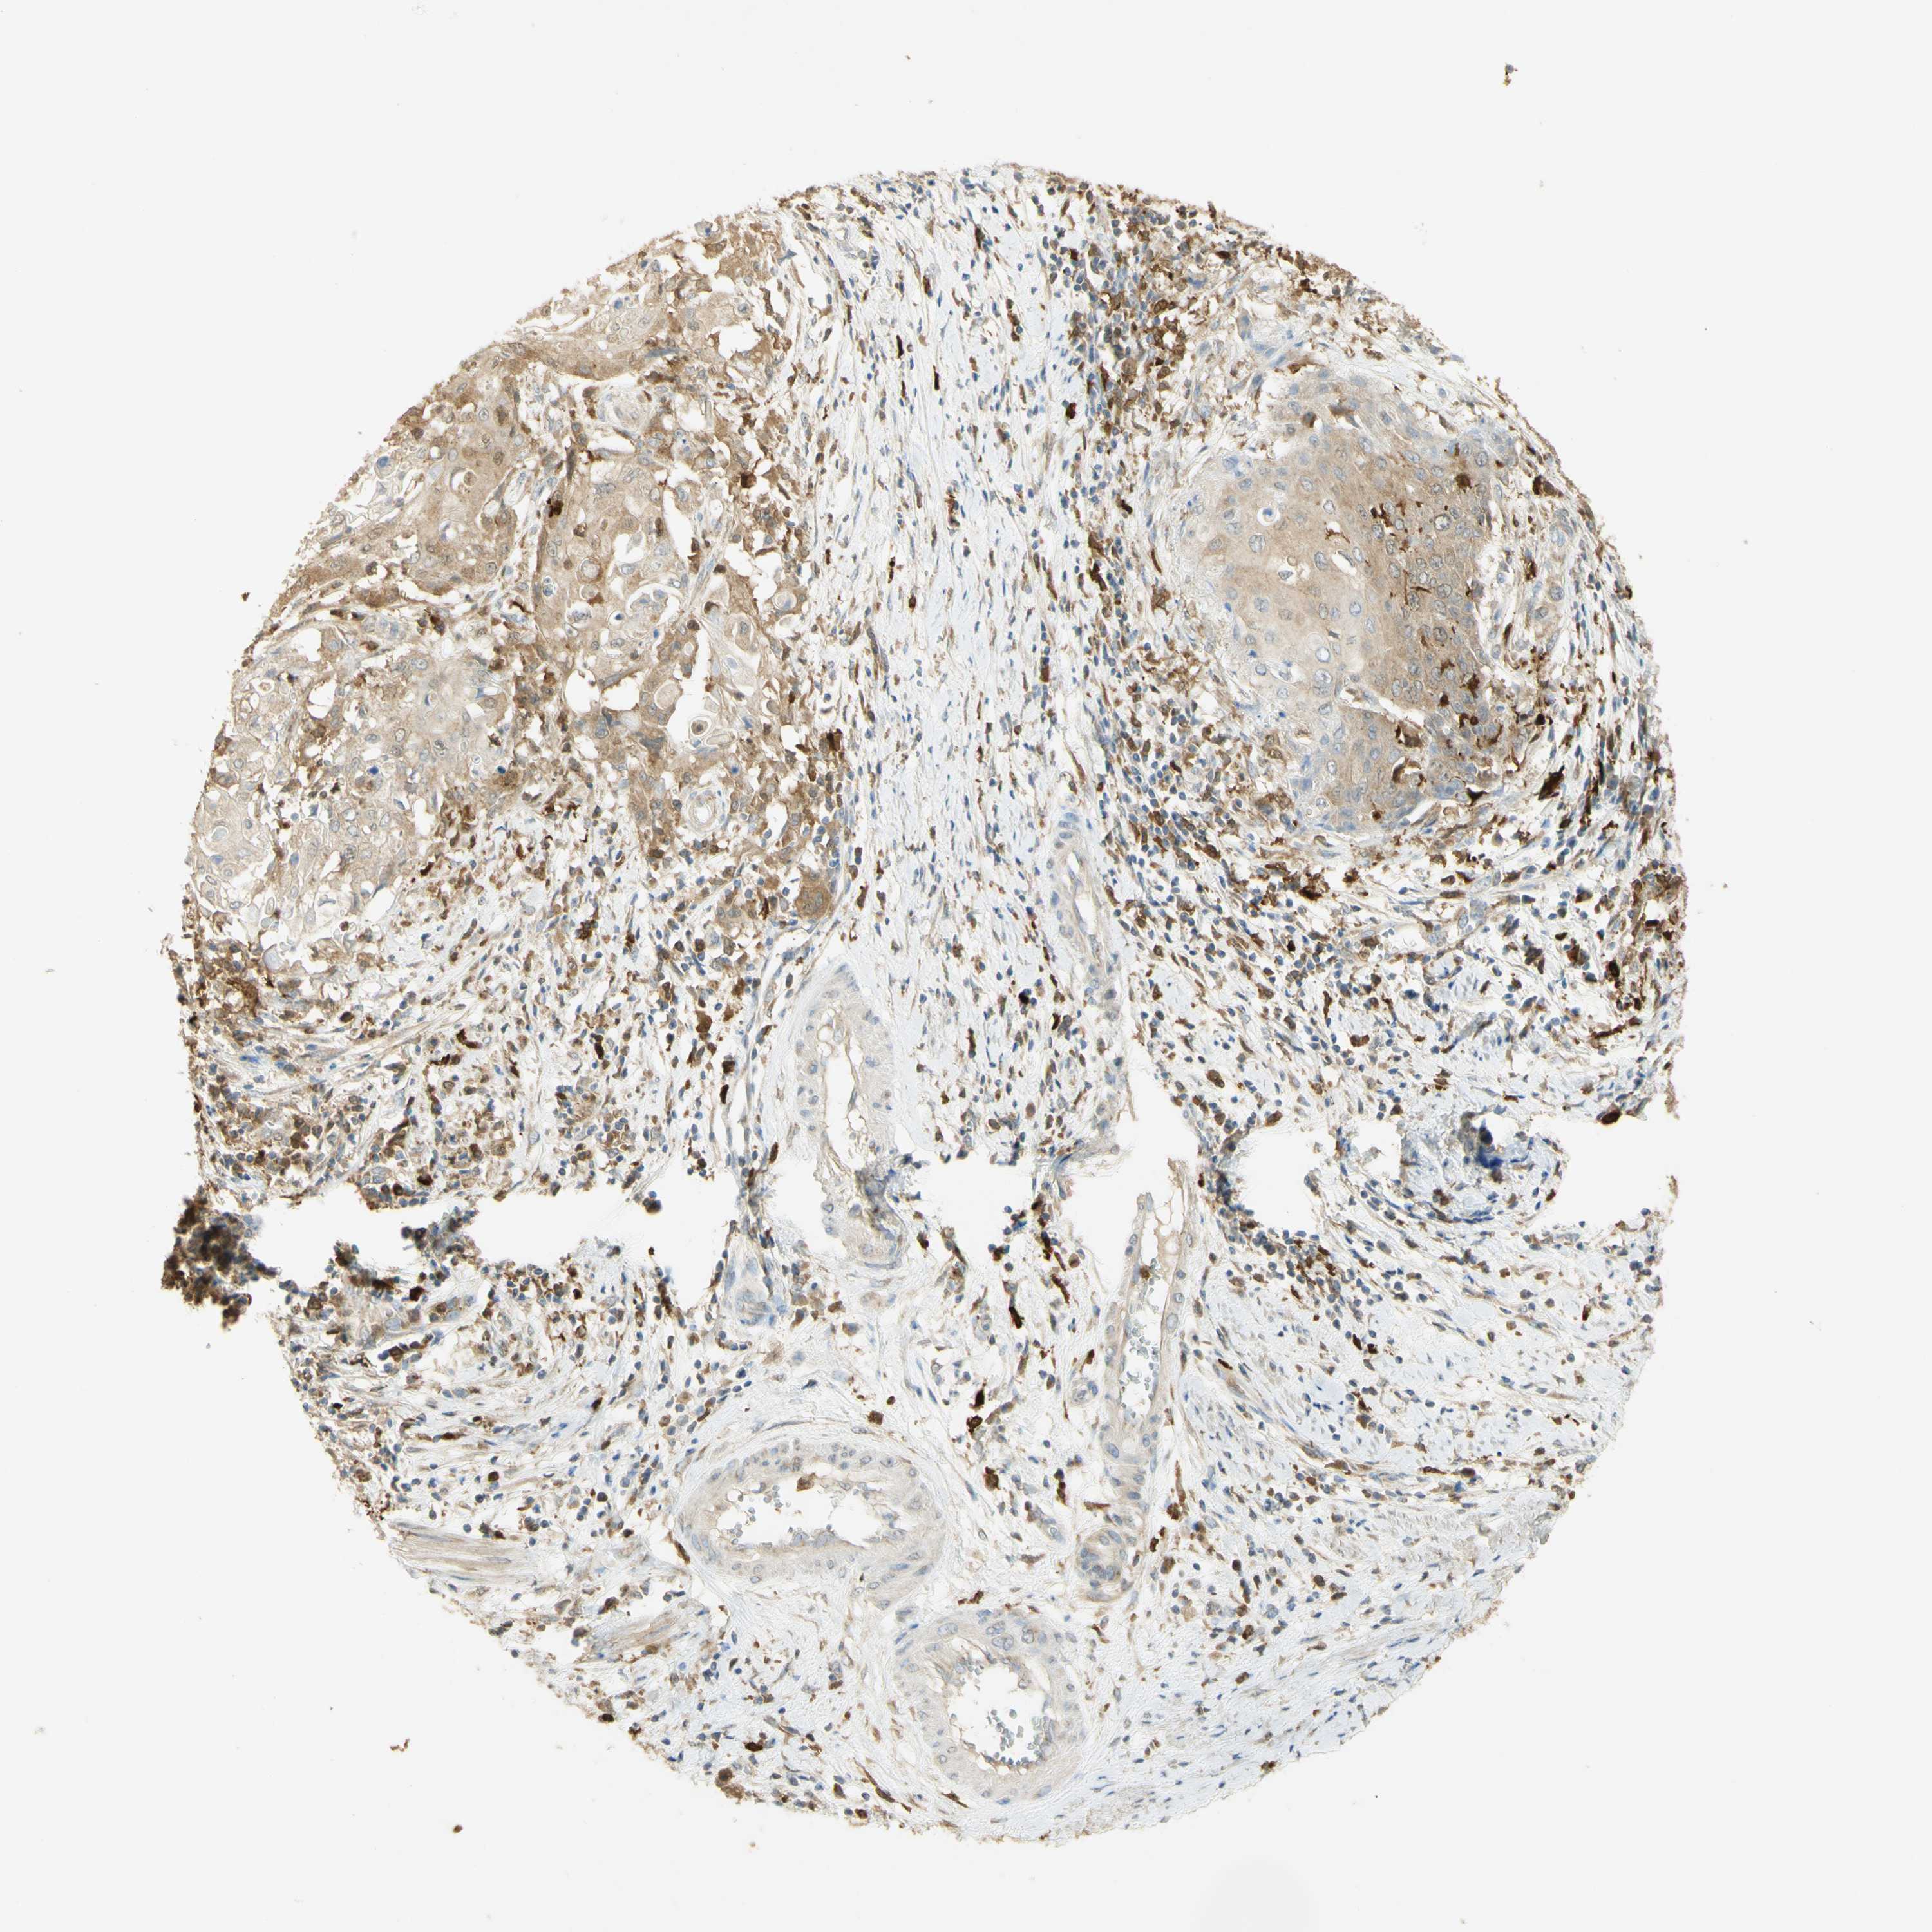

CERVICAL CANCER - Protein expressioni

A mouse-over function shows sample information and annotation data. Click on an image to view it in a full screen mode. Samples can be filtered based on level of antibody staining by selecting one or several of the following categories: high, medium, low and not detected. The assay and annotation is described here.

Note that samples used for immunohistochemistry by the Human Protein Atlas do not correspond to samples in the TCGA dataset.

Antibody stainingi

Antibody staining in the annotated cell types in the current human tissue is reported as not detected, low, medium, or high, based on conventional immunohistochemistry profiling in selected tissues. This score is based on the combination of the staining intensity and fraction of stained cells.

Each image is clickable and will lead to virtual microscopy that enables deeper exploration of all samples and also displays staining intensity scores, fraction scores and subcellular localization as well as patient and tissue information for each sample.

Antibody HPA003565

Antibody CAB005312

Squamous cell carcinoma, NOS

Adenocarcinoma, NOS